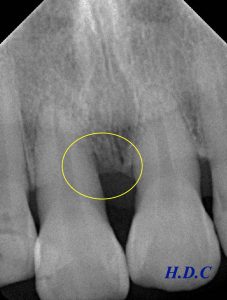

患者さんは30代の女性です。他院から歯周病治療の依頼で来院されました。前院でしっかり歯ブラシ指導を受けていたこともあり、プラークコントロールは良好で、歯肉に顕著な炎症所見は認められませんでした。しかし、歯周ポケット検査を行ったところ、上の前歯に6mmの深い歯周ポケットを認め、レントゲン上でも骨が溶けていることが確認できました(左下レントゲン黄色い枠の中、歯の根の周りの黒くなっている場所)。

左のレントゲンが初診時、右のレントゲンがエムドゲイン治療後2年半経過時です。

歯周病で溶けてしまった骨の再生が確認できます(黄色い枠の中)。外科治療前に6mmあった歯周ポケットも、2mmに改善しました。